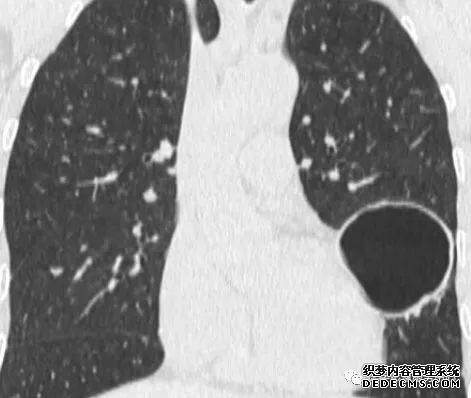

肺隔离症:易误诊为肺癌的占位性病变,肺穿刺禁忌!